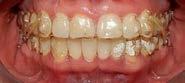

Estudio de caso

El paciente se presentó después de varios años de sufrir una herida traumática en sus dientes anterio res superiores. Las piezas 11 y 21 tenían varias fracturas, así como el borde incisal de la pieza 12. Por lo que él deseaba mejorar su estética bucal, y yo quería asegurarme de restaurar la funcionalidad y resisten cia también. El paciente necesitaba completar su tratamiento en un cor to periodo de tiempo, por ello debí realizar ajustes en mi flujo de traba jo. (Figura 1).